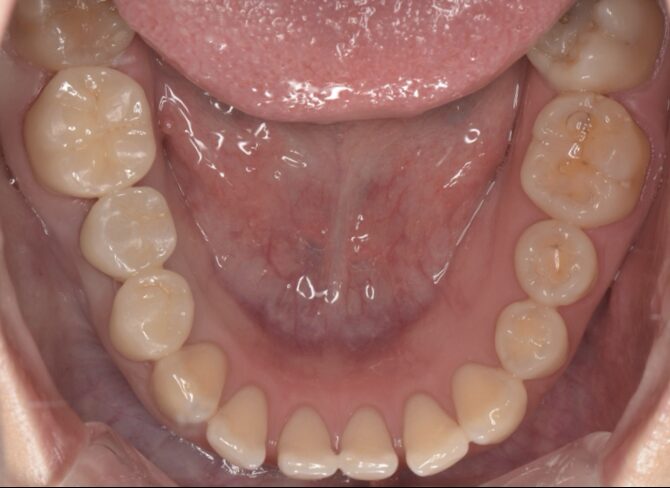

ポンティック下の残根を除去しインプラント治療した症例

After

| 治療内容 | インプラント、セラミッククラウン |

| 治療期間・治療回数 | 2ヶ月半 |

| 治療費用 | 869000円(税込) |